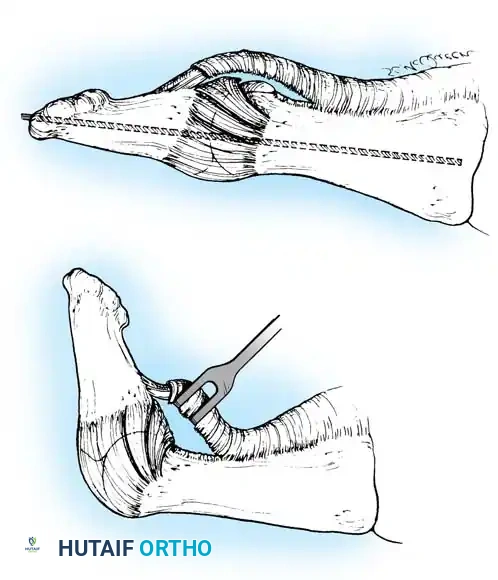

FIBULAR SESAMOIDECTOMY: PLANTAR APPROACH

• If a plantar approach (Fig. 78-21A) is chosen for fi bular sesamoidectomy, have an assistant hold the ankle dorsifl exed, and use a headlight for seeing into the full depth of the wound. Avoid the fl exor hallucis longus tendon and the neurovascular bundle to the fi rst web space.

• Flex and extend the hallux, and inspect the radiograph to locate the sesamoid. Beginning 1 to 1.5 cm distal to the metatarsophalangeal joint, make a longitudinal incision in the plantar surface of the foot, extending the incision proximally 3.5 to 4 cm between the fi rst and second metatarsals.

• Using small, blunt-tip dissecting scissors, identify the neurovascular bundle to the fi rst web space, and retract it laterally or medially, depending on the position of the sesamoid (Fig. 78-21B).

• Open the pulley over the fl exor hallucis longus tendon, and retract the tendon medially. This maneuver is made easier by having an assistant hold the foot in dorsifl exion at the arch with one hand and fl ex the metatarsophalangeal joint to relax the fl exor hallucis longus tendon with the opposite hand.

• At this point, the intersesamoid ligament should come into view; divide it completely (Fig. 78-21C). This may require moving the scalpel 1 or 2 mm laterally or medially to fi nd the groove between the sesamoids.

• Incise the cleavage plane between the two sesamoids, while retracting the fl exor hallucis longus muscle medially and the neurovascular bundle laterally.

• Grasp the fi bular sesamoid with a strong pick-up or small Kocher clamp, and remove the lateral head insertion of the fl exor hallucis brevis muscle on the proximal end of the sesamoid using direct vision (loupe magnifi cation makes this easier, but is not necessary).

• When the medial and proximal restraints of the sesamoid have been released, sever the attachment of the adductor hallucis muscle to its lateral distal edge close to the bone with a scalpel or scissors.

• Sever the last attachment of the sesamoid distally where the plantar plate continues its distal insertion into the proximal phalanx (Fig. 78-21D).

• Excising the sesamoid does not release the adductor insertion on the base of the proximal phalanx. This can be released through the plantar incision. Continuing to retract the neurovascular bundle laterally and the fl exor hallucis longus muscle medially, and adducting the hallux, while the opposite index fi nger palpates the adductor, helps identify the structure (Fig. 78-21E).

• Using right-angle retractors, expose the adductor, excise a small section of the tendon, and move the hallux medially.

• At the conclusion of this procedure, the surgeon should be unable to palpate any restraining structures on the fi bular side of the metatarsophalangeal joint. The transverse natatory fi bers in the dorsal aspect of the web space should be released manually. All restraints pulling the hallux laterally (except the extrinsic tendons) must be removed.